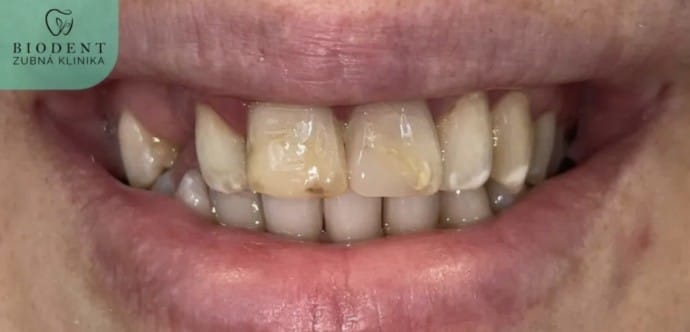

Na bezplatnej konzultácii vám navrhneme plán liečenia. Obyčajne sa na zuby, ktoré sú poškodené viac ako 40%, odporúča náhrada pomocou moderných keramických faziet alebo zirkónových koruniek, ktoré majú oproti kompozitným výplniam množstvo výhod - pevnosť, estetika a trvanlivosť!

- zub poškodený kazom viac ako 40%

- zmena farby, pigmentácia skloviny, ktorú už nemožno odstrániť bielením